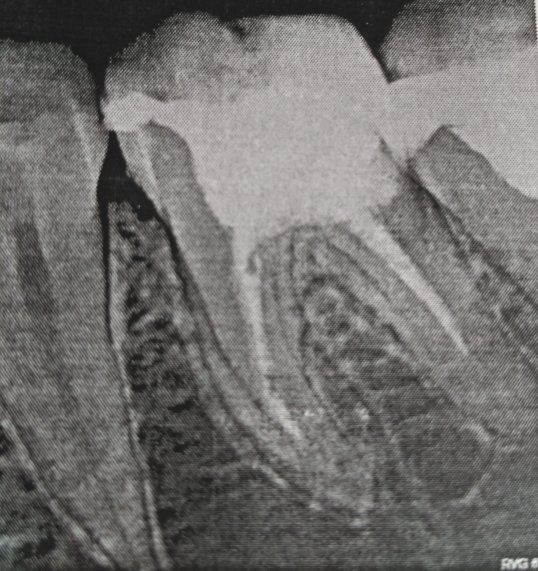

Я вам уже ответил, боль в седьмом зубе связана с хроническим воспалением на верхушках данного зуба. Обратитесь на очный прием в стоматологическую клинику. Мост необходимо снимать и перелечивать опорные зубы.